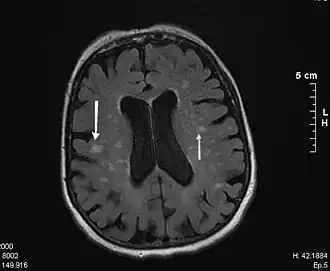

La leucoaraïose ou leucaraïose (LA) est une leucoencéphalopathie, une maladie du système nerveux central provoquée par des altérations vasculaires (microangiosclérose) avec épaississement fibrohyalin[1], au niveau de la substance blanche du cerveau. Ces altérations, principalement localisées dans l'espace périventriculaire, se présentent généralement sous la forme de modifications multifocales ou diffuses de tailles variables[2].

L'imagerie par résonance magnétique (IRM) en phase T2, et la tomodensitométrie (scanner) montrent la présence de lésions de la substance blanche, disséminées dans le cerveau ; ces images, sous forme d'un hypersignal, témoignent de lésions vasculaires. L'évolution de ces lésions peut aboutir à donner une image de « cerveau en gruyère ».